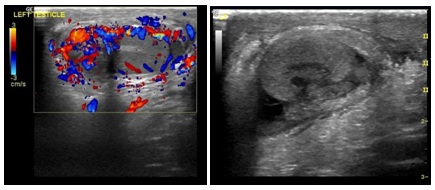

Figure 4One (1male) was with testicular twisting.